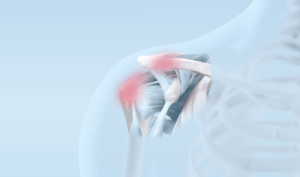

Dekompression, Kalkentfernung, AC-Resektion

Grössere Kalkformationen, schmerzhafte Schultereckgelenke, chronische Entzündungen der Schultersehnen und/oder des Schleimbeutels lassen sich in seltenen Fällen konservativ nur ungenügend oder gar nicht behandeln.

Fortbestehenden Beschwerden im Bereich dieser Strukturen müssen deshalb gelegentlich chirurgisch behandelt werden. Diese Eingriffe erfolgen in der Regel in arthroskopischer Technik (Schlüssellochtechnik).